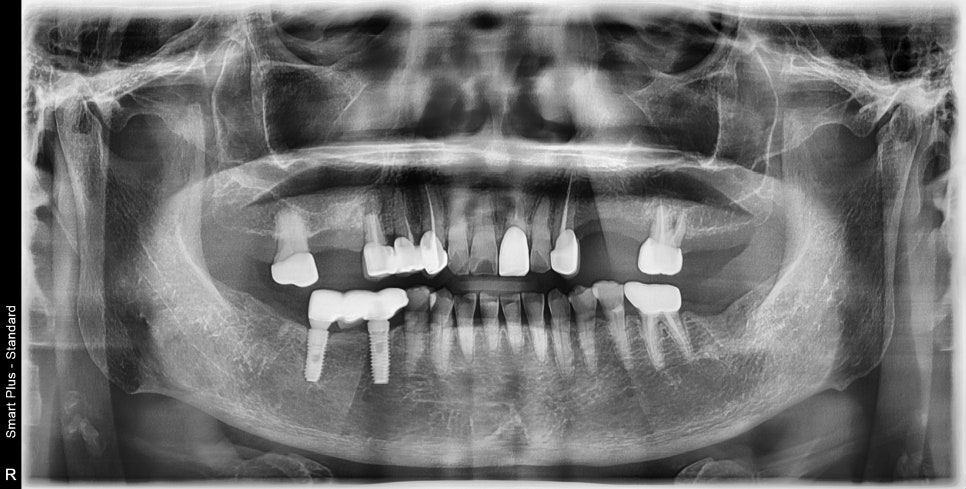

좌우 치아가 3개가 빠진 상태에서 틀니 사용을 권유받으시고 사용 중이었습니다.

앞서 말씀드린 바와 같이 이 정도 치아의 개수에서는

틀니보다 임플란트 치료를 하시는 것이 치료 방법과 기간이 훨씬 단순하고

다른 치아를 보존하는 목적에서도 좋습니다.

틀니를 제작할 당시 해당 치과에서는 임플란트가 불가하다고 설명을 들으셨습니다

엑스레이를 볼 때 상악동 거상술 같은 추가적인 치조골 이식술이 필요해 보이지만

임플란트가 불가능한 상황은 아니셨기 때문에

먼저 불편감을 해소하고 치료를 진행하기로 했습니다.